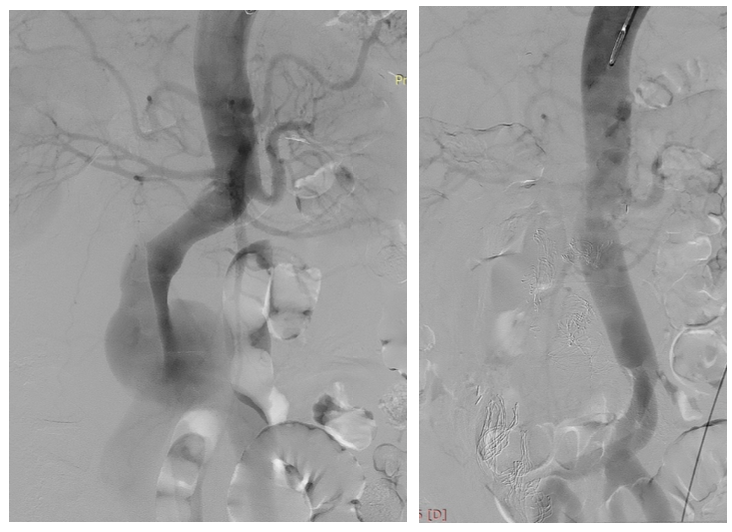

病例二:复杂B型夹层,行体外开窗+左锁骨下动脉支架

对于累及主动脉弓的B型夹层,采用左锁骨下动脉开窗,小覆膜支架技术,既延长了锚定区,保证破口的封闭,又确保了左锁骨下动脉的供血。